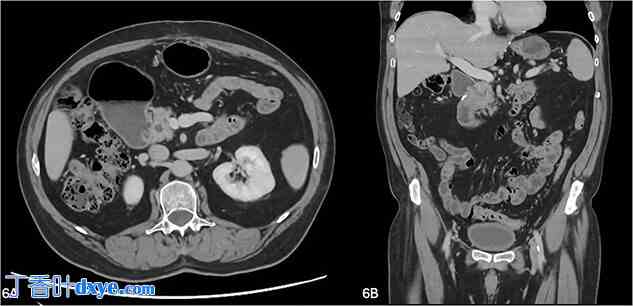

患者术后第八天出现反复反流和嗳气症状。再次进行CT和超声内镜检查,结果显示在十二指肠第二段(环状胰腺已分离)附近有1-2厘米的积液。超声内镜抽吸脂肪酶,结果显示脂肪酶为88,931 U/l,提示少量胰漏。在同一次手术中,患者接受了十二指肠扩张术,在荧光透视引导下置入CRE™球囊扩张器,将十二指肠管腔扩张至20毫米直径。此手术缓解了他的症状,目前病情依然良好。4个月后复查CT,显示先前转折点附近长期存在的胃扩张和十二指肠上段得到改善,十二指肠周围脂肪条带和十二指肠壁增厚消失(图6)。

图6.

(A, B) 4个月后复查CT,显示先前转折点附近胃扩张和十二指肠上段得到改善,十二指肠周围脂肪条带和十二指肠壁增厚消失。